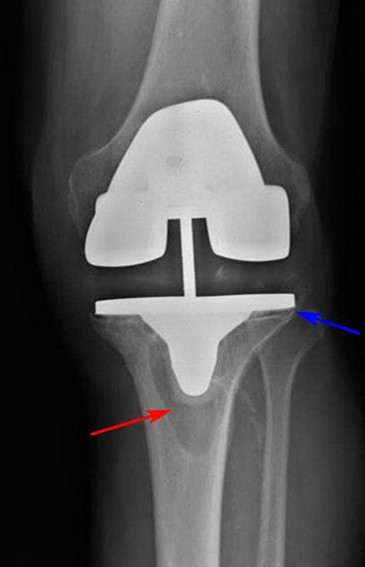

Приклад 2. Хвора  М. 68 років. Діагноз: лівобічний деформівний IVст. гонартроз, стан після ТЕП лівого КС (2014р.). Під час виконання оперативного втручання компоненти ендопротезу встановлені в варусному положенні. Асептична нестабільність компонентів ендопротеза, тотальна  нестабільність зв’язкового апарату компонентів колінного суглоба (2017 р.)  Хворій виконано ревізійне ендопротезування: видалення компонентів ендопротезу, виявлений дефект виростку великогомілкової кістки тип Т2А за класифікацією АОRI [G.A. Engh, C.H. Rorabeck, 1997]. Враховуючи стан зв’язкового апарату використаний зв’язаний ендопротез типу Hinch.